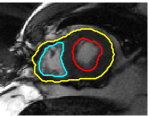

Figures 8 and 9 shows some sample tracking results of the proposed method and Medviso on full cardiac cycles of two different cases on both the LV dataset and the RV dataset. The ground truth (yellow) is superimposed when available. A summary of the results on the entire datasets is shown in Table I. The accuracy with respect to ground truth is measured using average perpendicular distance (APD) and dice metric (DM) for left ventricle, and Hausdorff distance (HD) and DM for the right ventricle. These metrics are chosen since they are the standard ones used on these datasets. Both qualitative and quantitative results show that our proposed method leads to more accurate segmentation of the ventricles and thus leads to less interaction than segmentation propagation schemes in than Medviso.

| initial | ventricle tracked (red - algorithm result, yellow - ground truth) | |||

|---|---|---|---|---|

|

Medviso

![]() |

our method